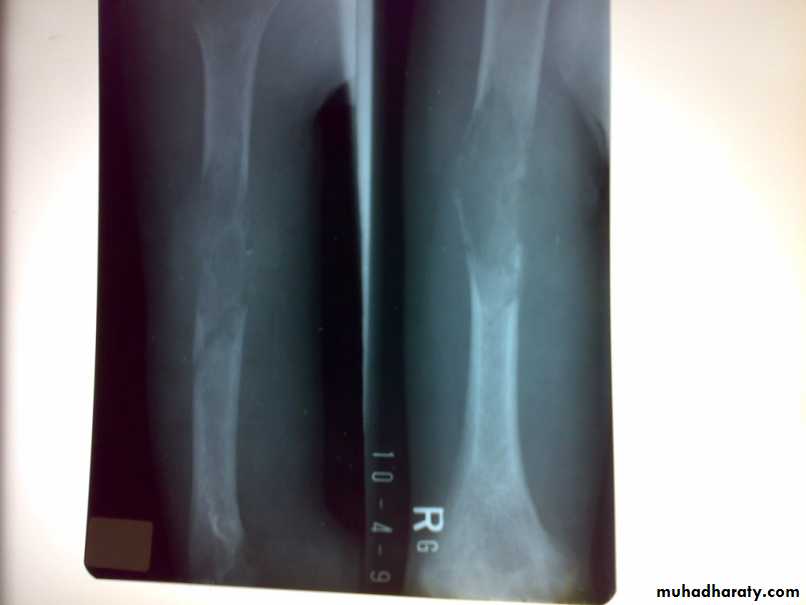

Definition: it is rare primary malignant tumor of vascular endothelial tissue of bone marrow (neuroectodermal origin).it give rise florid periosteal reaction and early metastases

Site: usually diaphysis of long bone.

X-RAY:

show ill-define osteolytic lesion with overlying periosteal reaction in form of layers (onion peel). Radioisotope scanning show active area.